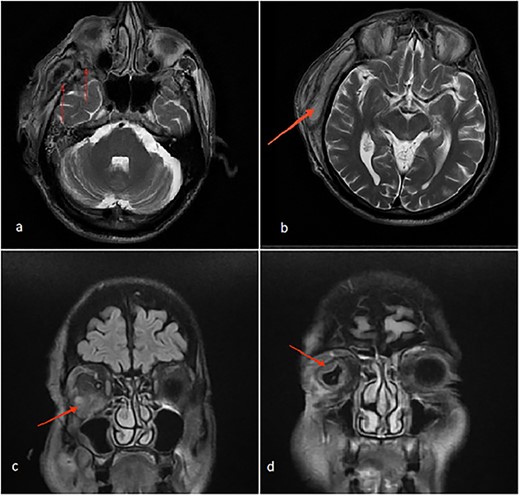

The patient’s head and neck were imaged using magnetic resonance imaging (MRI) and computed tomography scan, which revealed the presence of abscess collections in the submasseteric space, pterygomandibular space, deep temporal space and infratemporal abscess spreading to the orbital cavity through a bony defect in the lateral orbital wall, all of which were not addressed during the first procedure (Figs 2 and 3).

(a) Axial MRI of the head: a dumbbell-shaped lesion (red arrows) representing an infratemporal abscess invading the orbital cavity through the bony erosion of the lateral orbital wall. (b) Abscess localization in the deep temporal space (red arrows). (c, d) Coronal MRI of the head and neck shows an orbital abscess (red arrows) and endopthalmitis (red arrows).

Axial MRI of the head, a dumbbell-shaped lesion (red arrows) representing an infratemporal abscess invading the orbital cavity through the bony erosion of the lateral orbital wall.

Most cases of odontogenic orbital complications arise from upper jaw tooth infections [4]. What is unique about our case is the unusual route by which the infection spread into the orbit. In our case, the hypothesized path of spread started from the lower third molar infection to both the submasseteric and pterygomandibular spaces and then passed into the infratemporal fossa, where a focus of abscess was loculated, making its way into the orbit through a bony defect in the lateral orbital wall, forming an interesting dumbbell-shape appearance on MRI (Fig. 2a).